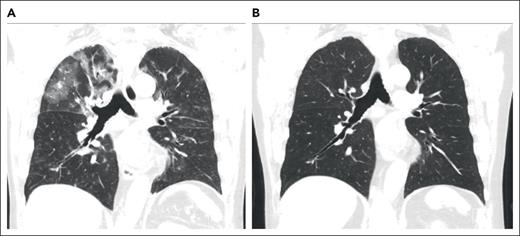

A 73-year-old man with a history of myelodysplastic syndrome, who received a nonmyeloablative allogeneic peripheral blood stem cell transplant (PBSCT), presented with progressive dyspnea, a nonproductive cough, and hypoxemia a year after HCT. Weeks before presentation, the patient was newly diagnosed with cGVHD of the skin. A chest computed tomography (CT) scan showed upper lobe predominant ground-glass opacities in a subpleural and peribronchovascular distribution (Figure 1A). The patient was treated for infectious pneumonia with levofloxacin without improvement. Clinical history did not reveal an antecedent exposure to medications associated with OP. Bronchoscopy with bronchoalveolar lavage (BAL) was performed, and microbiology culture results for bacterial, fungal, and viral pathogens were negative. On the basis of a lack of association with known pulmonary toxic medications or infectious agents, HCT-OP was diagnosed, and prednisone (1 mg/kg per day) was initiated with a slow taper over 4 months. The patient’s clinical symptoms rapidly resolved, including his skin cGVHD, and radiological improvement was achieved (Figure 1B).

Figure 1.

Representative coronal images from a noncontrast chest CT scan. (A) CT scan of the chest, demonstrating a right-sided upper lobe–predominant, peripheral ground-glass opacity at the diagnosis of organizing pneumonia. (B) CT images after 4 months of treatment with prednisone, demonstrating resolution of opacities.